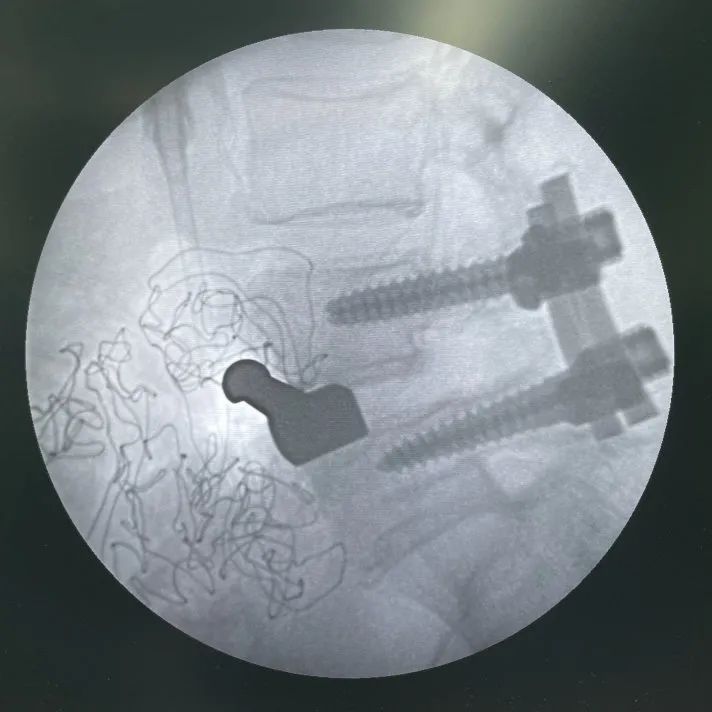

示意-正視圖:頭側(cè)固定夾打入已完成,尾側(cè)正在使用固定夾開路器開路

示意-側(cè)視圖:頭側(cè)固定夾打入已完成,尾側(cè)正在使用固定夾開路器開路

正視圖:頭尾側(cè)固定夾均已完全打入

直視圖:cage與固定夾完全打入后

L3/L4常規(guī)OLIF融合器植入

L3/L4 、L4/L5椎間植骨

最終透視

術(shù)后一周左右,將根據(jù)情況,擇期為患者拆除、更換后路釘棒系統(tǒng)